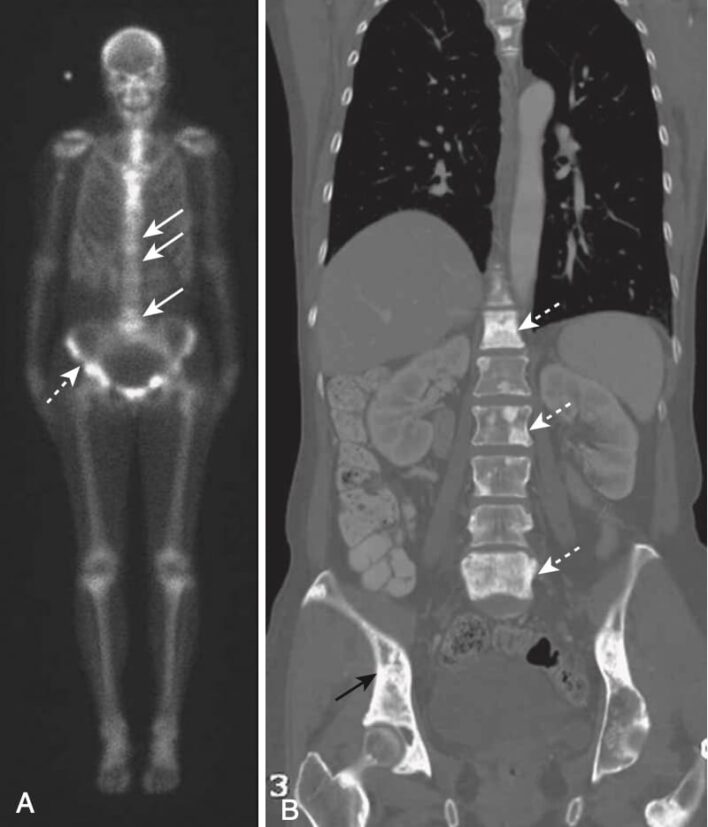

- Thăm dò hình ảnh sàng lọc được lựa chọn hiện nay để phát hiện di căn cột sống là xạ hình xương technetium-99m (99mTc) (quét xương với phóng xạ hạt nhân). Technetium thường được liên kết với methylene diphosphonate (MDP) để vận chuyển 99mTc vào xương. Phương pháp xạ hình xương tương đối rẻ tiền, phổ biến rộng rãi và có thể sàng lọc toàn bộ cơ thể. Mặc dù xạ hình xương có độ nhạy cao để phát hiện sự hiện diện của di căn, nhưng chúng không đặc hiệu lắm. Trong nhiều trường hợp, một thăm dò khẳng định, thường là chụp X quang thường quy, là cần thiết để loại trừ các nguyên nhân khác gây ra sự hấp thu bất thường của chất phóng xạ như gãy xương, nhiễm trùng và viêm khớp (Hình 13).

- MRI có thể phát hiện những thay đổi của di căn cột sống thậm chí sớm hơn so với quét phóng xạ hạt nhân, và kỹ thuật hiện nay có thể cho phép sàng lọc nhanh toàn bộ cơ thể tương tự như quét xương bằng phóng xạ hạt nhân.